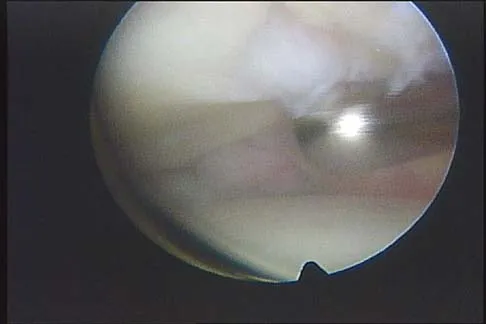

A 16-year-old girl has a painful foot mass. A radiograph, MRI scan, and biopsy specimens are shown in Figures 35a through 35d. What is the most likely diagnosis?

Synovial sarcoma should always be considered in the differential diagnosis of a foot mass; however, the histopathology shows a typical example of PVNS, with hemosiderin, giant cells, and synovium. Synovial chondromatosis would have metaplastic cartilage in the synovium. The radiograph shows subtle erosion of the lateral cortex of the cuboid, and the MRI scan shows a soft-tissue mass. Ghert MA, Scully SP, Harrelson JM: Pigmented villonodular synovitis of the foot and ankle: A review of six cases. Foot Ankle Int 1999;20:326-330. Jones BC, Sundaram M, Kransdorf MJ: Synovial sarcoma: MR imaging findings in 34 patients. Am J Roentgenol 1993;161:827-830. Sartoris DJ, Resnick D: Magnetic resonance imaging of pediatric foot and ankle disorders. J Foot Surg 1990;29:489-494.